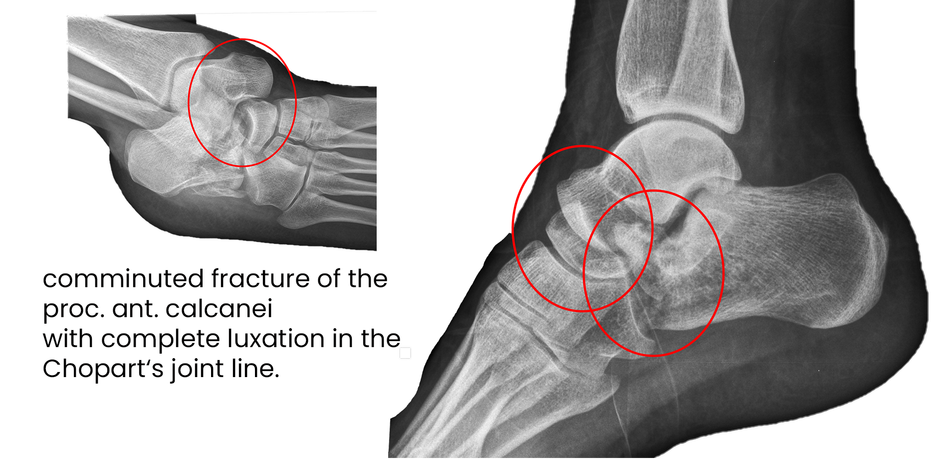

case 17LC, 29 years old, female, fall from horse

with the foot caught in the stirrup

"atypical fracture", surgery 19 hours after trauma